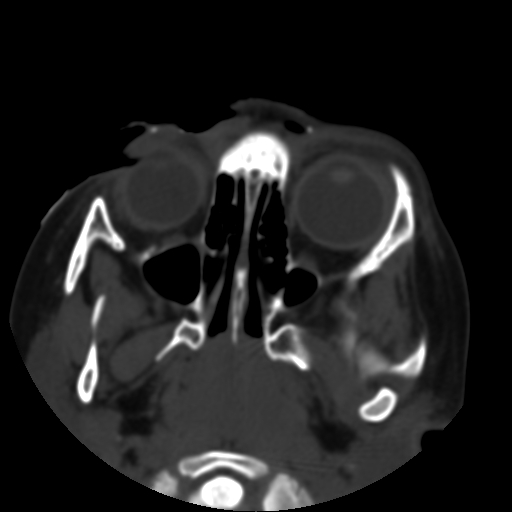

以下是引用深泽交通医院在2009-10-16 8:25:00的发言:[br]右眼环出血伴异物

以下是引用拾荒者在2009-10-17 18:38:00的发言:[br]鼻面部皮下积气,右侧睑缘及眼球壁高密度异物影,左侧眼球壁晶状体内侧缘处是圆形低密度影。低密度异物?应提请眼科医生注意。